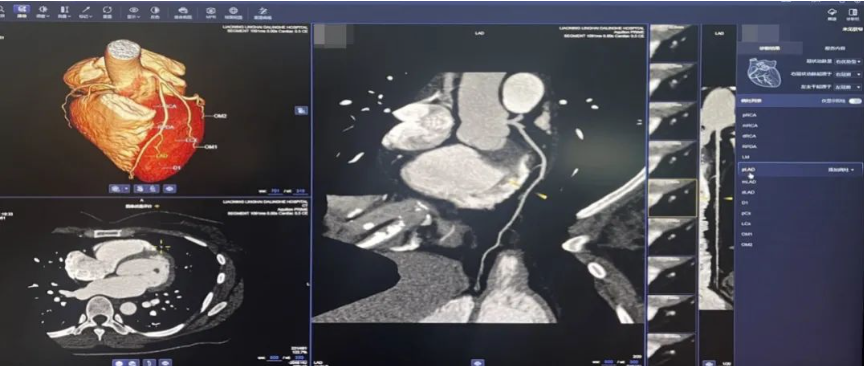

AI冠脉、头颈部CTA血管斑块辅助检测

能自动识别血管,完成血管分段的标识,同时能自动完成血管狭窄和斑块性质评估,为斑块风险提供建议,提高诊断效率,促进冠心病、诊治标准化,帮助医生快速明确病变位置和范围。同时,基于重组的图像可以对常见血管病变进行智能诊断,包括血管狭窄及斑块分析、颅内动脉瘤等,实现CTA检查全流程覆盖。